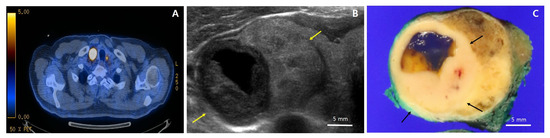

2. Case Presentation